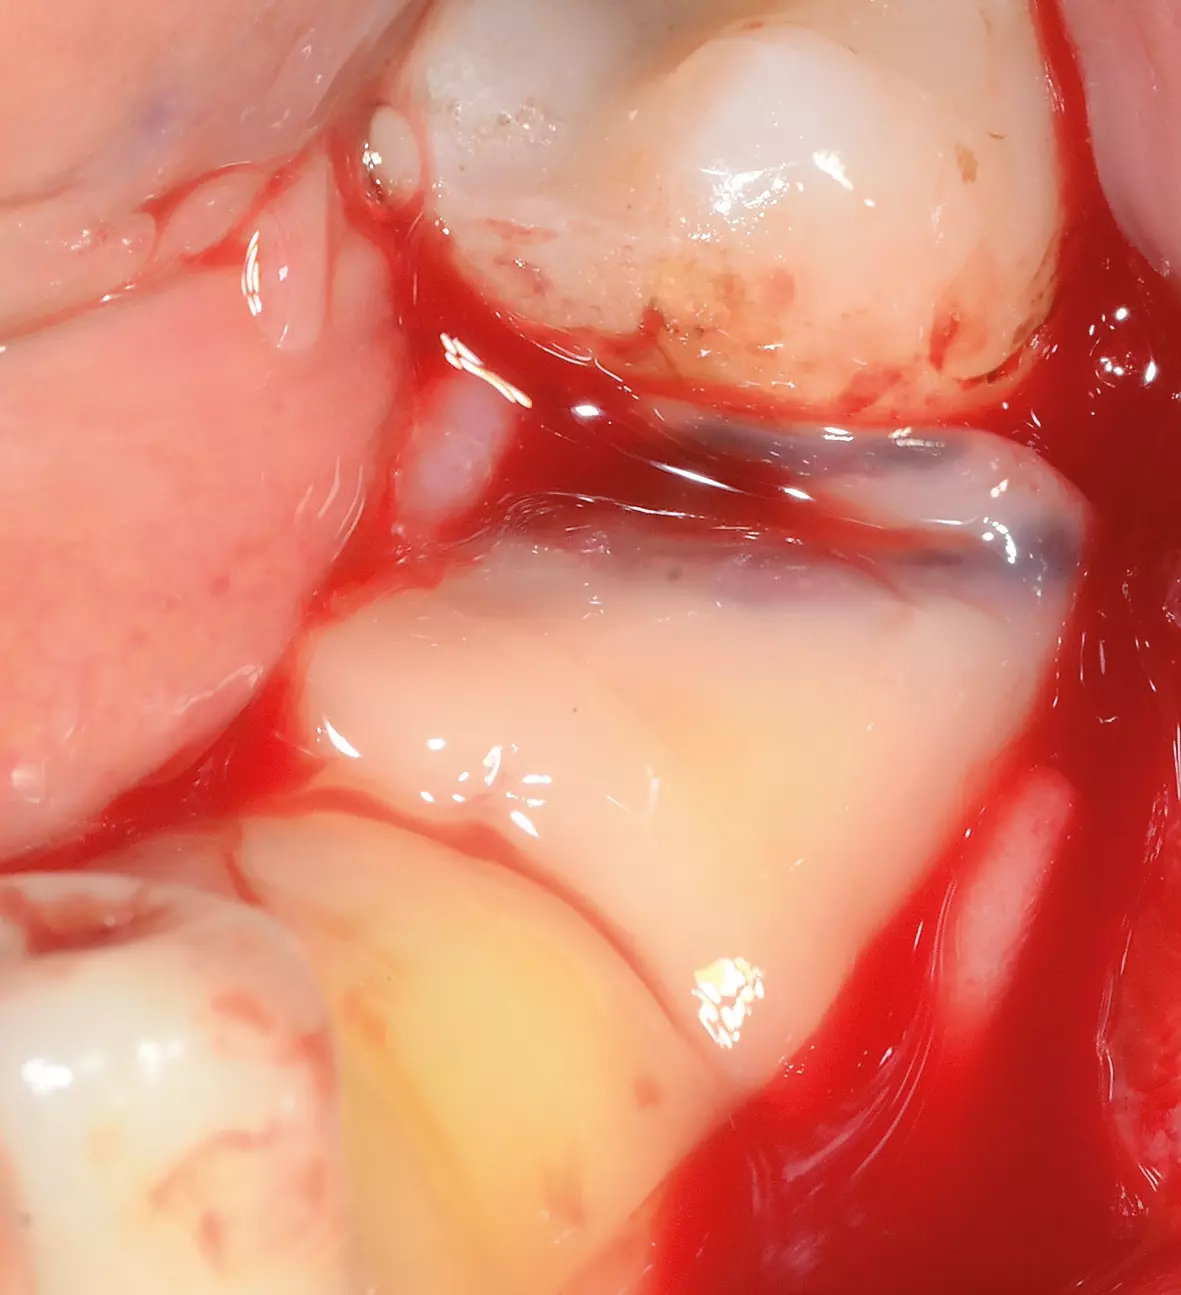

Nach 6 Monaten Einheilzeit wurde die Gitterentfernung mit gleichzeitiger Implantation durchgeführt. Nach Vorbereiten der Patientin und entsprechender Lokalanästhesie wurde eine marginale, entlang an Zahn 34 und der vorhandenen Narbe krestale leicht linguale Schnittführung gewählt. Zur Darstellung des Gitters wurde ein vestibulärer und lingualer Mukoperiostlappen präpariert. Das Gitter zeigte sich regelrecht eingeheilt und zum Teil sogar knöchern bedeckt (Abb. 28). Zur Entfernung des Gitters wurde dieses an der mittleren Sollbruchstelle aufgebrochen und der linguale und vestibuläre Anteil getrennt entfernt (Abb. 29a und b). Anschließend wurde das Implantatlager vorgebohrt und entsprechend dem Bohrprotokoll des Herstellers aufbereitet (Abb. 30). Der Planung folgend wurden dann drei Implantate (Bego SC) regio 35 mit 4,1 x 8,5 mm, regio 36 mit 4,5 x 8,5 mm und regio 37 mit 4,5 x 7mm gesetzt (Abb. 31). Für eine Nachkorrektur der Knochenkontur um die gesetzten Implantate wurde nochmals DBBM eingebracht, mit einer Kollagenmembran (Geistlich Bio-Gide) und PRF abgedeckt und mit einer spannungsfreien Naht verschlossen (Abb. 32 und 33). Das postoperative Röntgenbild zeigt die drei gesetzten Implantate (BEGO SC) an den jeweils vorher digital geplanten Implantatpositionen (Abb. 34).